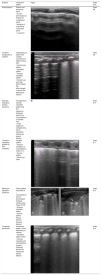

PneumothoraxThe sonographic features of pneumothorax are absence of lung sliding and of B-lines, exclusive presence of A-lines5 and the ‘lung point’ (LP), a sign that serves to locate the boundary between pneumothorax (absence of lung sliding) and any other lung pattern (with lung sliding) (Fig. 1, Video S5).

Pneumothorax. (A) Anterior longitudinal plane. Absence of lung sliding, absence of B-lines and clearly defined A-lines. (B) M-mode. Absence of lung sliding. Stratosphere sign: pleural line and clearly defined equidistant A-lines. (C) Transverse plane, 4th–5th intercostal space. Lung point (LP): sonographic sign that marks the boundary between pneumothorax (absence of lung sliding) and any other lung pattern (lung sliding). On ultrasound, pneumothorax is considered mild-moderate if the LP is in the mid-clavicular line or anterior axillary line and severe if it is posterior to the mid-axillary line.